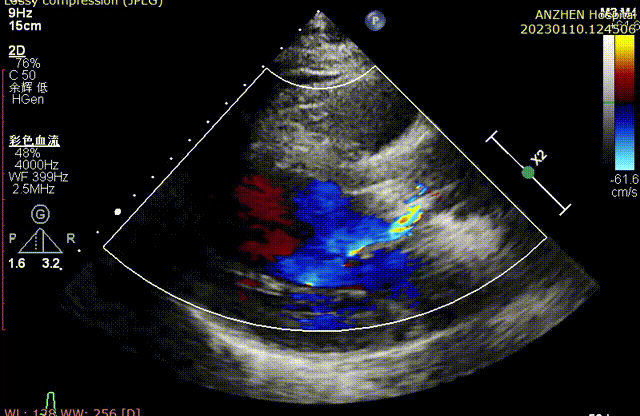

术前超声

术后超声

经DSA造影和超声等综合评估显示瓣膜释放位置完美,瓣膜工作稳定,术后即刻主动脉瓣上峰值流速:202cm/s、峰值压力阶差:15mmHg,平均压差:7mmHg,人工主动脉瓣瓣环内无反流,微量瓣周漏,患者临床症状和血流动力学明显改善。